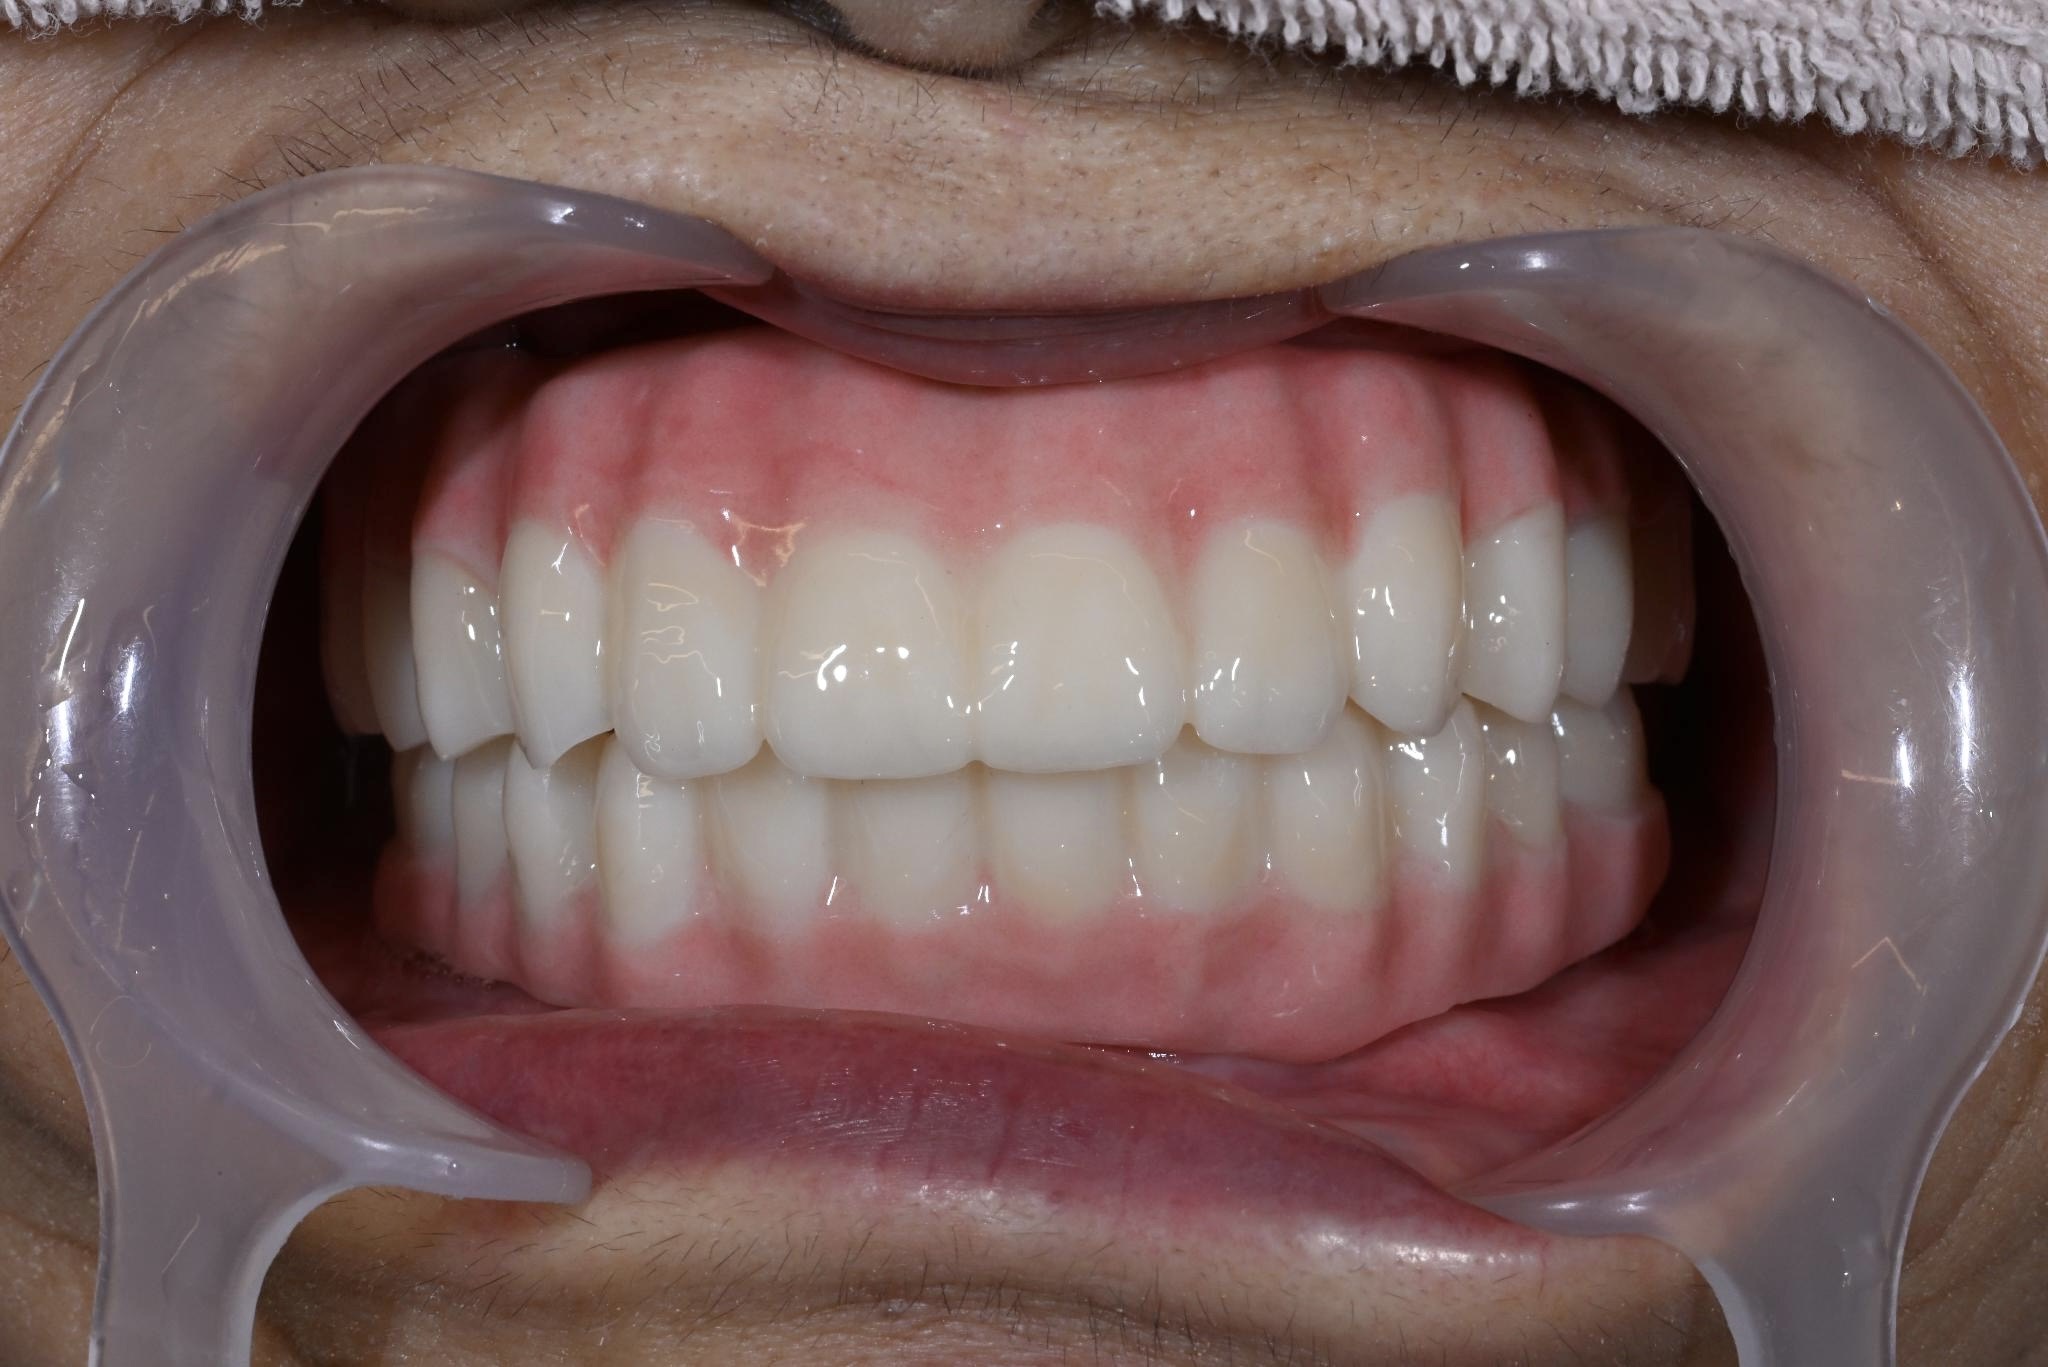

術後

内容 :上下顎オールオン4ザイゴマ4

費用 :6,132,800円

※モニター価格

期間 :半年

リスク:出血・腫れ・痺れ・痛み

上下総義歯を使用していましたが、食事や会話の度に歯茎に痛みが生じ、日常生活において多大なストレスを抱えていました。情報誌「グランザ」でこちらのクリニックを知り、義歯の悩みから解放されたいという切実な思いから相談に行くことに決めました。

過去に麻酔による全身痙攣の経験があることや骨粗鬆症の治療薬を服用中であることなど外科的処置に対するリスク要因を持ち合わせていました。ですが、丁寧なカウンセリングと説明を受け、取り外し不要な「固定式の歯」を得られることへの魅力が不安を上回り、手術をうけることにしました。

手術は計画通り進行し、術後の仕上がりにもとても満足しています。

長年苦しめられた義歯による痛みや不自由さから解放され、食事を楽しめるようになることが楽しみです。美しい見た目になったのでマスクを外して過ごせるようになることも嬉しいです。自分と同じように歯の悩みで苦しむ方にぜひ勧めたいです。